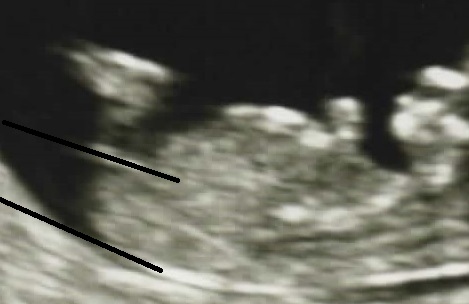

I've lost my mind; I'm drawing lines. All I need now is a protractor =)

Now I am confused. I thought boy at first but I see what you intended by drawing the lines, it does look quite parallel to the spine. It can definitely be a girl!

Just realised it does extend past the bottom so very confusing. Hope you hear pink xx

I could see this one going either way- but it does look more girly at the moment.